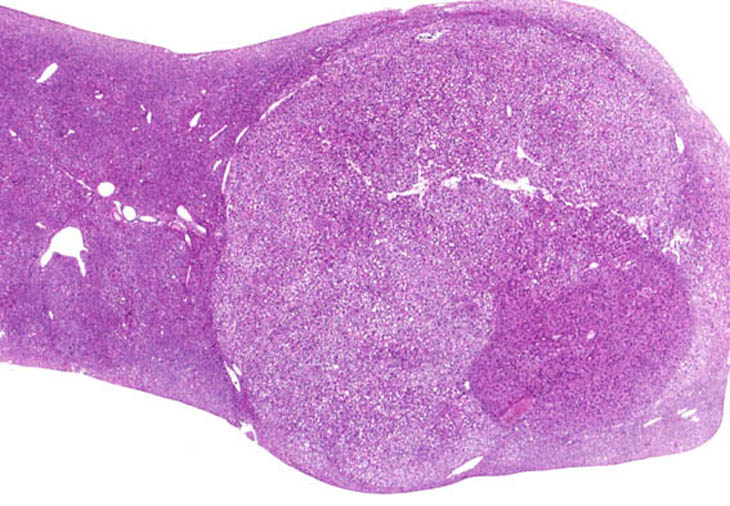

A hepatocellular carcinoma arising within a discrete hepatocellular adenoma.

A small area of carcinoma characterized by thickened trabeculae is arising within a large adenoma.